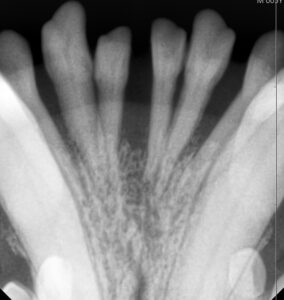

歯のレントゲンを撮ってみると歯周病により歯を支えている骨が溶けているのが分かります。

歯周ポケットが深く、揺れがあり、歯周病が重度に進行している歯は抜歯を行いました。